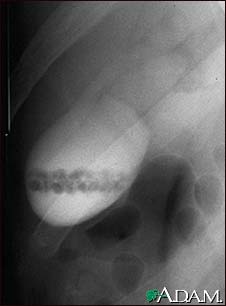

Gallstones, cholangiogram

A cholecystogram in a patient with gallstones.